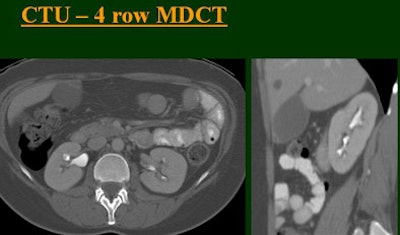

At the 2004 RSNA meeting in Chicago, Dr. Vassilios Raptopoulos from Massachusetts General Hospital and Harvard Medical School in Boston evaluated single-, four-, eight-, and 16-row detector scanners in 200 patients using a single-acquisition biphasic CT urography (CTU) protocol. As the number of detector rows increased, visualization -- especially of the calyces -- improved significantly.

"As we've been scanning through the kidneys, we've been noticing that there has been an increase in the quality images as we go from (single-) to four-, eight-, and 16-row detector scans," Raptopoulos said. "Our purpose, then, was to assess the quality of CTU with progressively improving CT technology from (single-) to 4-, 8-, and 16-row scanners, using a split-injection single scanning technique."

| Top to bottom: Split-bolus CTU improves significantly using a nearly identical protocol but with the addition of more detector rows, from single- (spiral), four-, eight-, and 16-row scanners. All images courtesy of Dr. Vassilios Raptopoulos. |

The single-row scanner required two breath-holds; the other scanners reduced scan time from about 20 seconds (four-slice) down to seven seconds (16-slice). Collimation for the single-row scanner was 5 mm, with 3-mm overlapping reconstructions. Collimation for the four-, eight-, and 16-row scanners was 2.5 mm, 1.5 mm, and 0.5 mm, respectively, with the patients scanned in a prone position.

Based on multiplanar reformatted (MPR) images, there was significant upscale improvement in calyceal detail from the isotropic images provided by single-detector scanning (median score 2) to four- (median score 3), eight- (median score 4), and 16-detector scanning, Raptopoulos said. On MPR images the calyceal were 1, 2, 3, and 5, respectively. The median ureteral filling was 4 for the upper and left-lower ureters, and 3 for the right-lower ureters.

"We're using this technique of biphasic injections not only in CTU, but in general abdominal scanning in trauma, in renal CT, and we can see the renal vessels quite well in relation to the collecting systems," Raptopoulos said. "Combined excretory- and parenchymal-phase CTU is a practical technique, allowing a decrease in patient scanning," he said. "Sixteen-row CTU with the patient in a prone position significantly improves the quality of the exam."